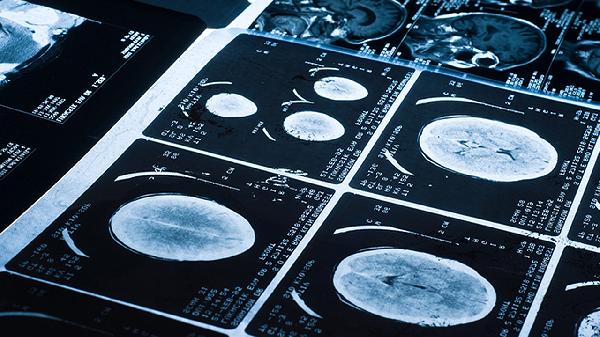

部分恶性肿瘤早期可能仅表现为肿瘤标志物轻微升高。非小细胞肺癌患者中约三成会出现细胞角蛋白19片段异常,尤其肺腺癌患者阳性率较高。需警惕持续性咳嗽、痰中带血、消瘦等报警症状,必要时通过支气管镜或CT引导下穿刺获取病理诊断。其他上皮源性肿瘤如乳腺癌、膀胱癌转移至肺部时也可能引起该指标变化。